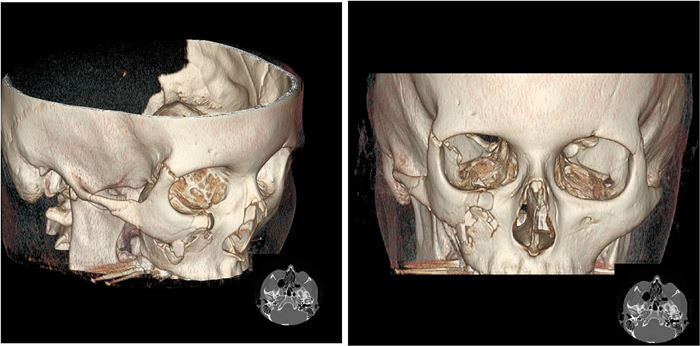

Diagnostyka obrazowa zatok staje się coraz bardziej istotna dla lekarzy dentystów, którzy posiadają w swoich gabinetach aparaty tomografii stożkowej (CBCT). W zależności od wielkości pola obrazowania w CBCT są widoczne fragmenty zatok szczękowych aż po całe zatoki szczękowe, a w badaniach o największym polu obrazowania wszystkie zatoki oboczne nosa, podobnie jak w badaniu medycznej tomografii komputerowej (TK). Z tego względu celem pracy jest przedstawienie najważniejszych zmian patologicznych zatok szczękowych, z którymi może się spotkać lekarz stomatolog, opisując badania tomografii stożkowej (CBCT).